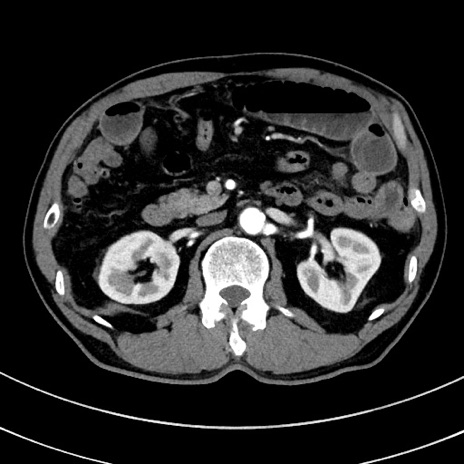

症例8(横断像)

【症例】 60歳代男性

【主訴】 黒色吐物

【現病歴】 4日前から嘔気自覚、2日前の朝食後にも嘔気あり、自分で手で嘔吐反射起こし嘔吐したところ血が混ざっていたため受診。

【既往歴】 5年前汎発性腹膜炎を伴う急性虫垂炎で手術、高血圧、前立腺肥大症、高脂血症

【身体所見】 腹部正中に手術癩痕あり 腹部平坦・軟圧痛なし膨満感あり

【データ】WBC 8400、CRP 4.54